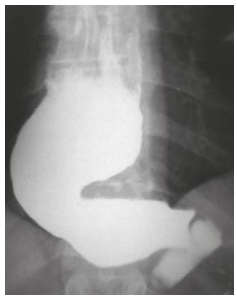

Mulher, 56 anos, portadora de megaesôfago grau IV (imagem abaixo). Admitida na enfermaria com desnutrição grave. Após instalação de sonda nasoenteral e dieta, passou a apresentar exames laboratoriais compatíveis com síndrome de realimentação.

Após realizar um ionograma, qual alteração foi identificada?